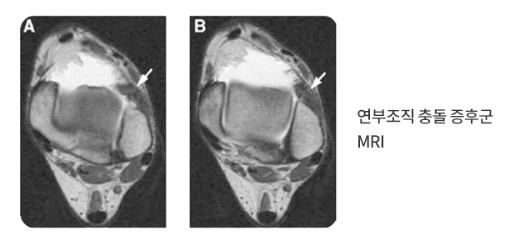

연부조직 충돌증후군

연부조직충돌증후군.PNG

연부조직 충돌증후군은 이상증식으로 인해 두꺼워진 연부 조직이 눌리면서 발목 앞쪽으로 통증을 일으키는 것을 말하는데요.

앞쪽외측인 전외방에 흔히 발생하는 연부조직 충돌증후군의 가장 큰 원인은 발목염좌입니다. 대부분의 환자들은 발을 삔 적이 없다고 기억을 못 하는데요. 정작 수술을 해보면 인대 손상 흔적으로 염좌가 확인되는 경우가 많습니다. 그만큼 생활 속에서 일어난 작은 염좌가 발목에 좋지 않은 영향을 미치는 것이지요.